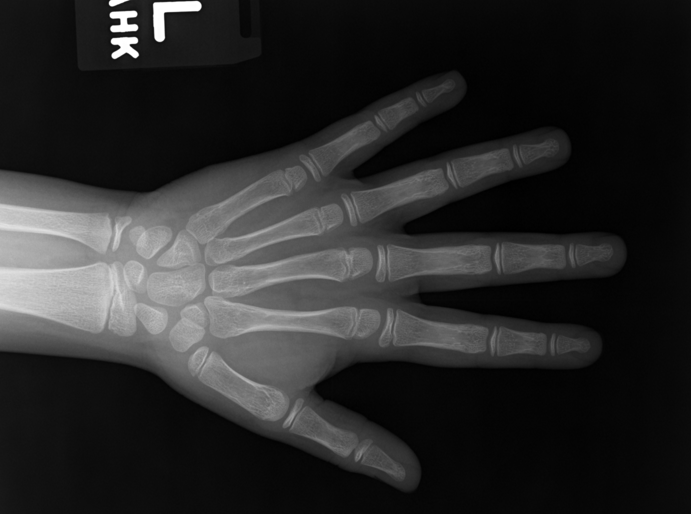

Several results from our method are shown in Fig. 7. The left column is the original input image. The right two columns are the soft tissue and bone image, respectively. It can be told that the soft tissue image is smooth as we assumed. Meanwhile, the bone image has better image contrast as desired. Moreover, our method can reach real-time performance on these X-ray images. The running time of our method on these images is reported in Table I.

Refer to caption

(a) original

(b) soft tissue

(c) bone (α=1.34𝛼1.34\alpha=1.34)

(d) original

(e) soft tissue

(f) bone (α=1.08𝛼1.08\alpha=1.08)

(g) original

(h) soft tissue

(i) bone (α=1.42𝛼1.42\alpha=1.42)

(j) original

(k) soft tissue

(l) bone (α=1.49𝛼1.49\alpha=1.49)

Figure 7: More results by our method. Input X-ray images (left), our estimated soft tissue (middle) and estimated bone image (right).